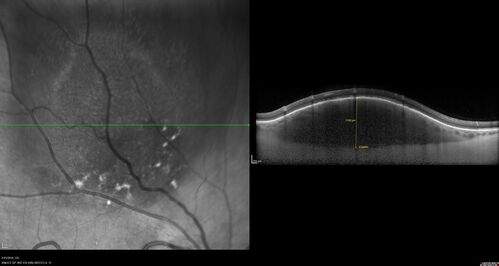

Amelanotic Choroidal Nevus

60 year old man. Nevus is stable over 6 years. Images are Photo, FAF, OCT, FA, ICG, and B-Scan

Amelanotic Nevus - OCT findings